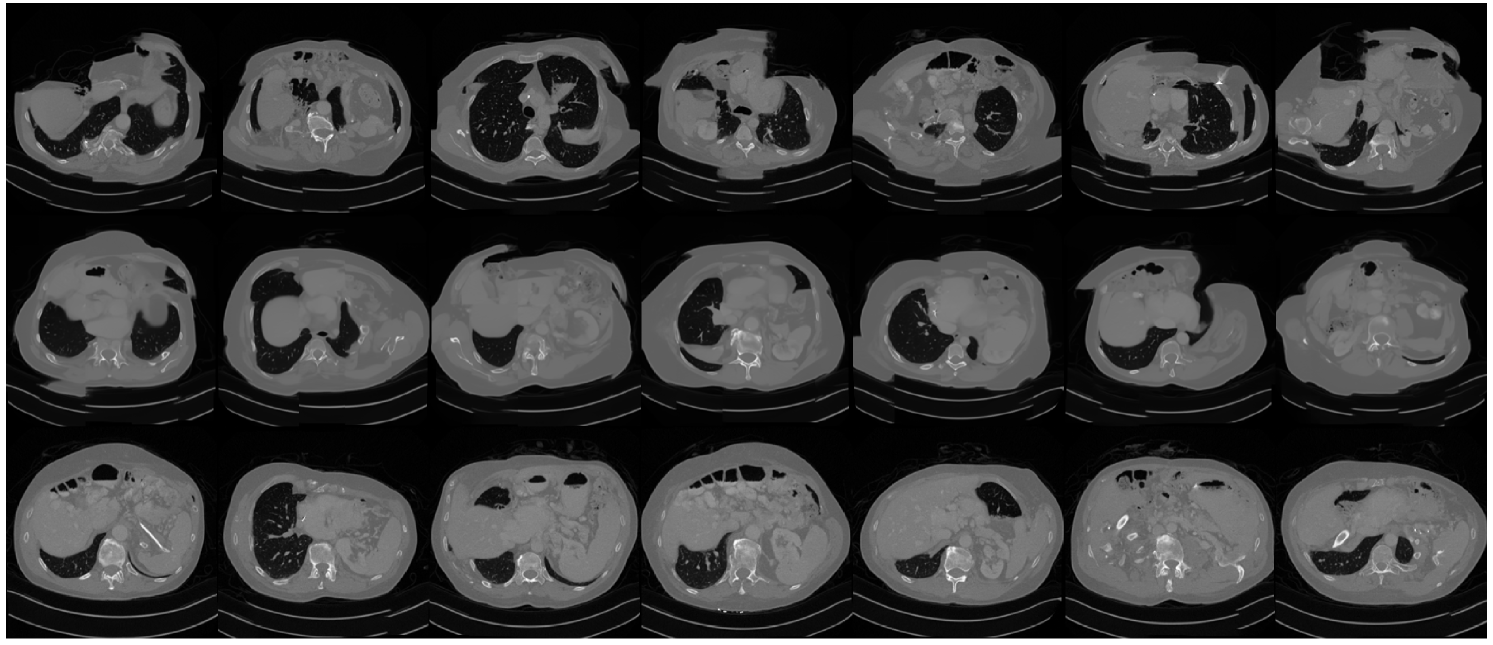

Our proposed method is able to learn a reasonable prior for whole images, despite never being trained on any whole images. Fig. 4 shows generation results for the CT dataset using three different methods. The top row used the network trained on whole images; the middle row used the method of [wang2023patch] except that the entire image is never supplied to the network either at training or sampling time; the bottom row used the proposed method. The middle row shows that the positional encoding does ensure reasonably appropriate generated patches at each location. However, simply generating each of the patches independently and then naively assembling them together leads to obvious boundary artifacts due to lack of consistency between patches. Our proposed method solves this problem by using overlapping patches via random patch grid shifts, leading to generated images with continuity throughout.

Refer to caption

Figure 4: Unconditional generation of CT images. Top row: generation with a network trained on whole image; middle row: patch-only version of [wang2023patch]; bottom row: proposed PaDIS method.